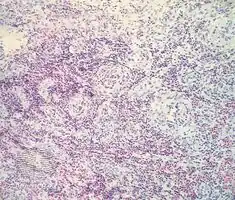

Angiolymphoid hyperplasia with eosinophilia/pathology